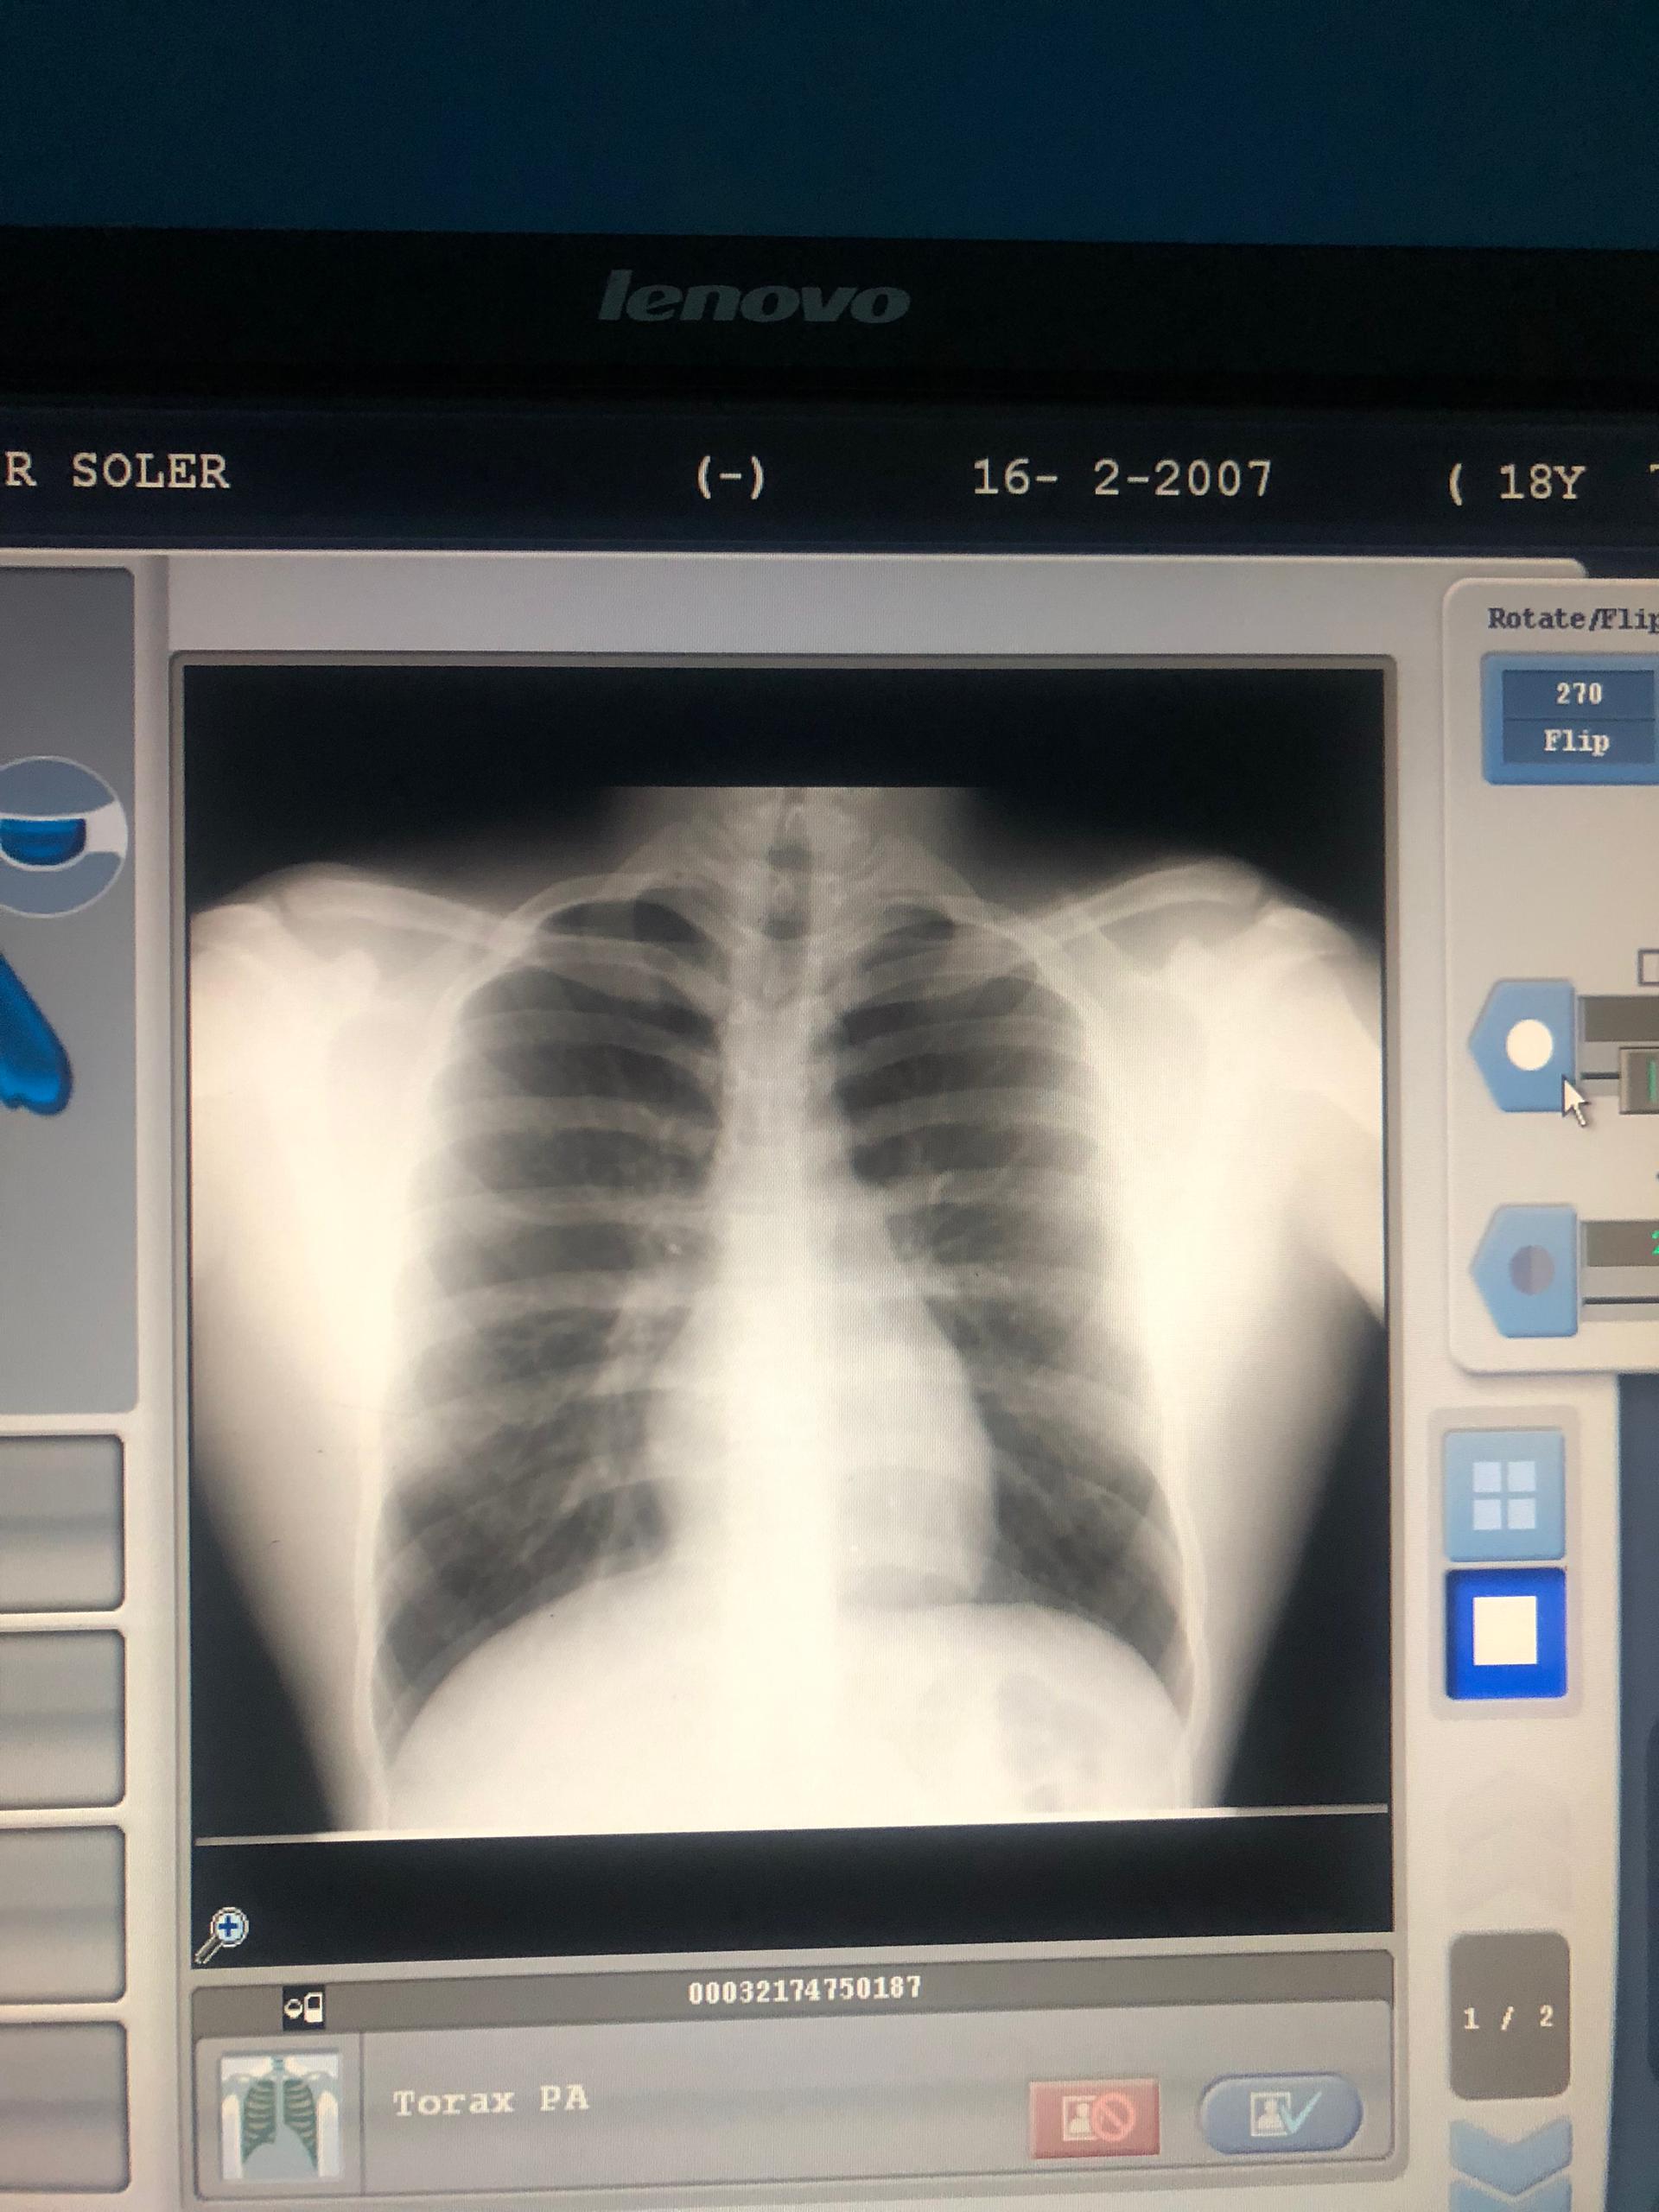

Fue una noche en que no se lo recomiendo a nadie, ni deseo a mi peor enemigo. Esto es una sensación que el simple hecho de toser, toser y no poder respirar es de lo peor. Esa noche me nebulicé para que pudiera entrar oxígeno y calmar la situación; sin embargo, sabía que tenía que ir al doctor para ver qué era lo que tenía. Primero fui al radiólogo, para hacerme una placa de rayos X. La chica, al ver mi placa, me comentó que era un patrón de neumonía que, si no me cuidaba, podría estar al borde de otro posible ataque.

It was a night I wouldn't recommend to anyone, nor wish on my worst enemy. It's a feeling that just coughing, coughing and not being able to breathe is the worst. That night I used a nebuliser so that oxygen could get in and calm the situation down; however, I knew I had to go to the doctor to see what was wrong with me. First I went to the radiologist to have an X-ray. The girl, upon seeing my X-ray, told me that it was a pattern of pneumonia and that if I didn't take care of myself, I could be on the verge of another possible attack.